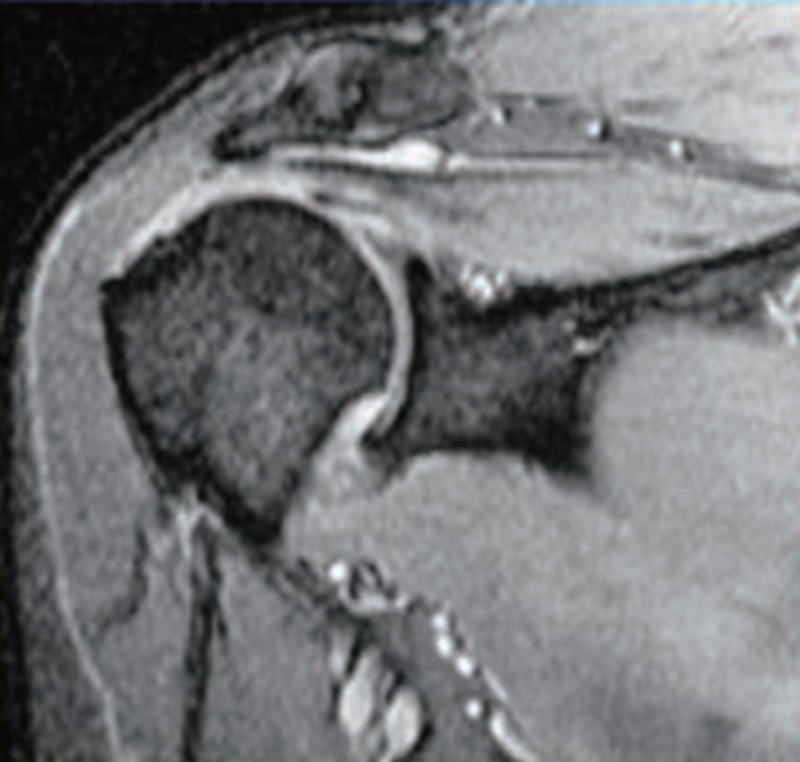

斜冠状位可以很好地判断冈上肌损伤的情况,T1像可以显示肌腱完整性的丧失,但T2像更为清晰,尤其是T2压脂像,去除了脂肪组织的干扰,可以清晰显示冈上肌撕裂后在局部造成的水样高亮信号影(图8)。在斜冠状位上还可以观察肌腱向内侧回缩的程度。

图8 MRI示冈上肌全层撕裂